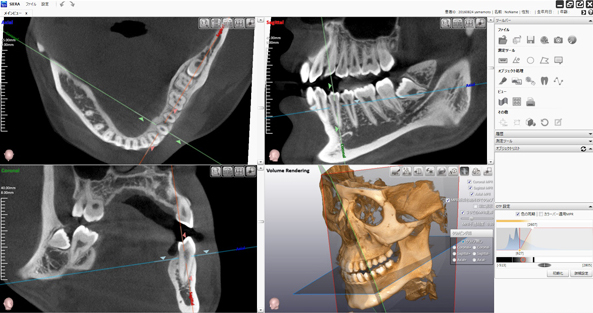

当院で行う親知らずの抜歯の特徴は「CT分析」があげられます。

一般的に歯科医院にあるレントゲンは「二次元」です。

当院には二次元よりも詳細に分析できる「三次元」のCT装置を導入しています。

三次元撮影装置(CT)を利用すると、二次元のレントゲンでは確認することができなかった部分まで事前に確認することができるようになります。

歯科医療において「見える」「見えない」は治療のクオリティに大きな差を生みます。

ましてや、外科処置が必要な場合や、近くに血管・神経が通っている場合はなおさらです。